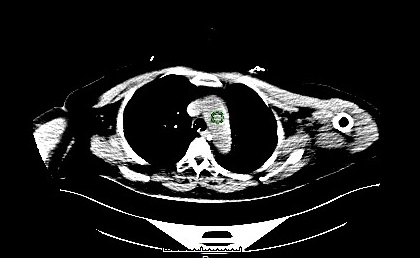

Contrast triggering start

Contrast HU reached the trigger value